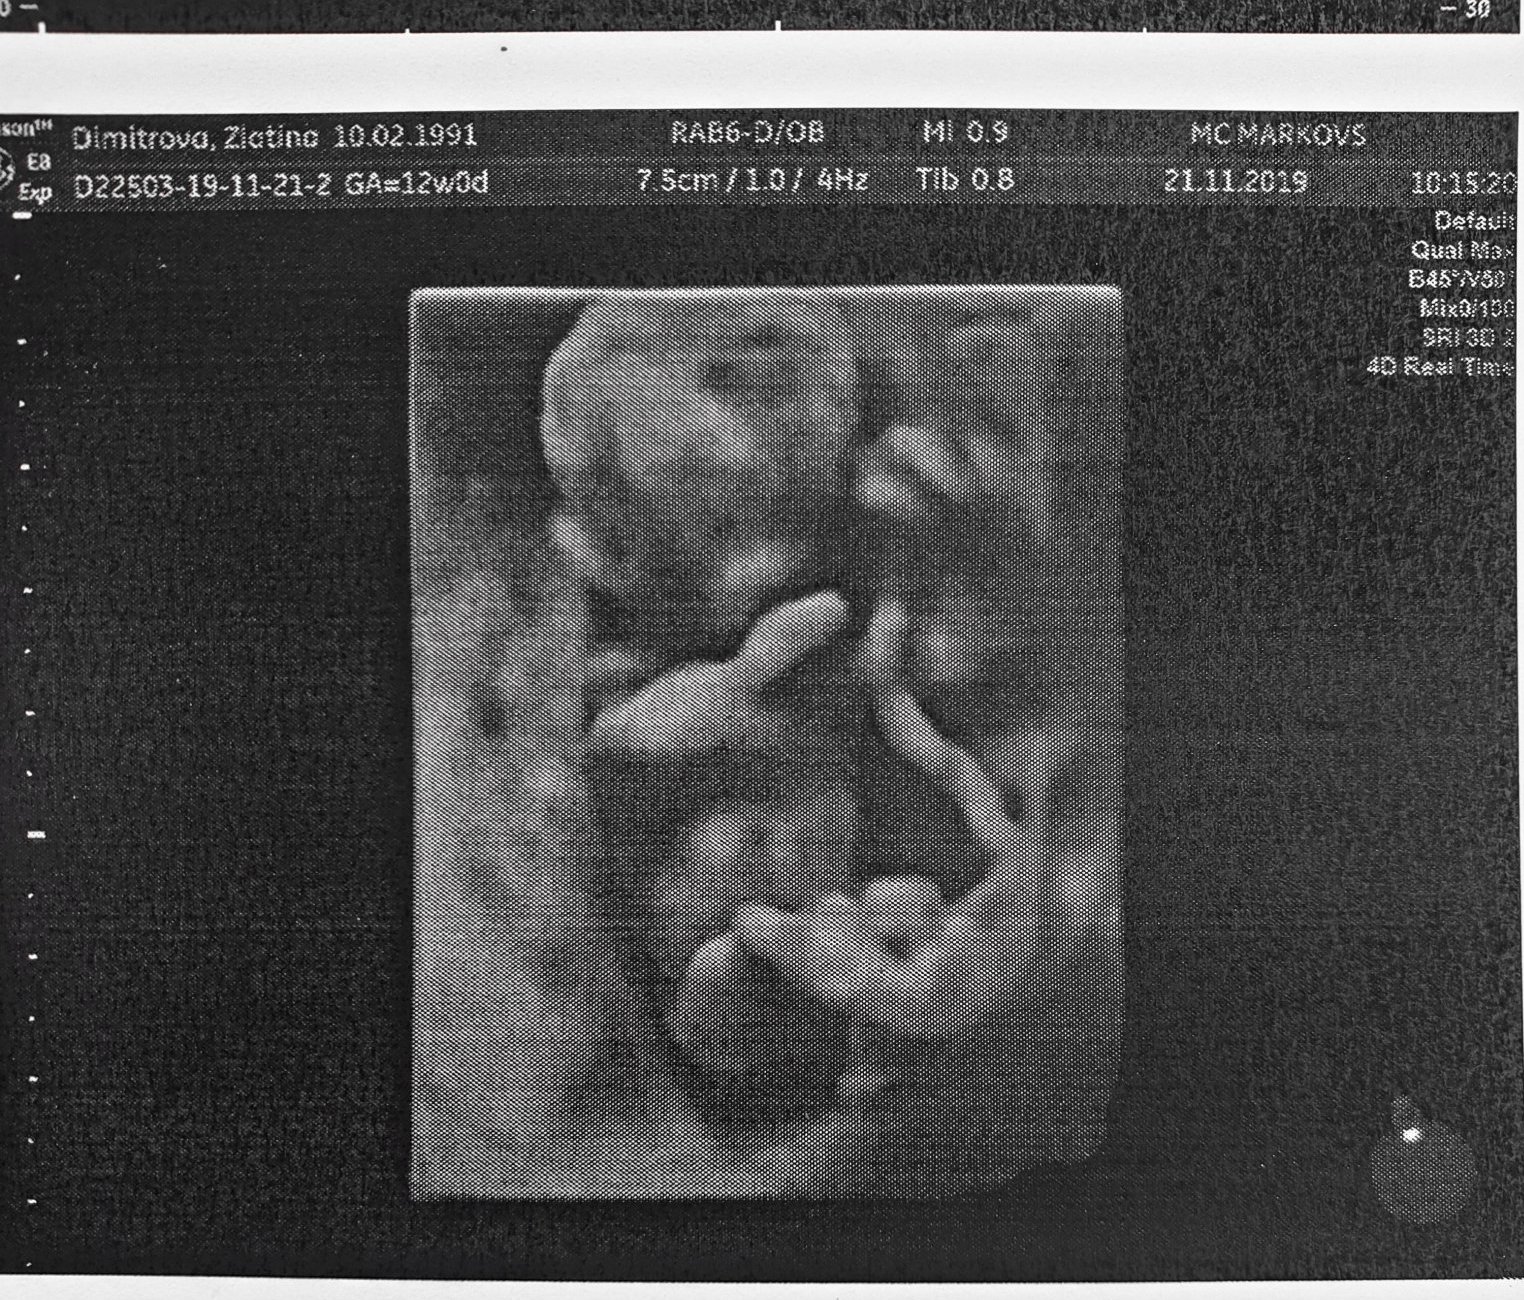

Момичета, влизам набързо да се отчета. Бяхме днес на ранна морфология в Марковс при д-р Атанасова. Много съм доволна, беше много внимателна и обстойна.

На бебето всичко, което му гледаха и измерваха е супер за сега. Върви 5 дена напред, но било нормално до 20с. Криеше се доста с гръб, но после се показа и си седеше с кръстосани крака през цялото време. На 90% е момиче, но все пак каза, че след 14с може да се каже със сигурност. Утре ще отида до Майчин дом да ми вземат кръв, че днес много се забавихме.

Та ето я кръстосалата крака госпожица Grinning